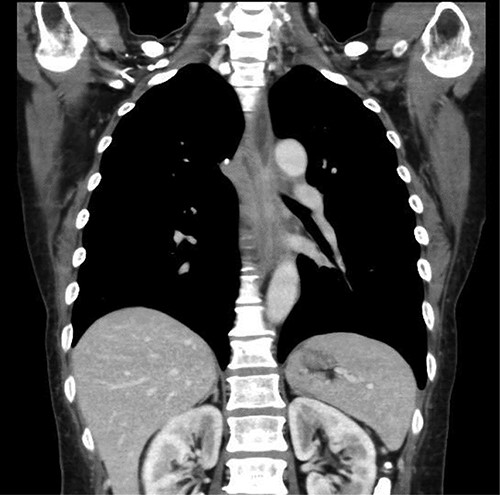

Preoperative computed tomography (CT) and barium meal studies were performed. The CT findings showed circumferential wall thickening with infiltrative change at the middle of the intrathoracic esophagus, with luminal dilation of the oral side of the stenotic esophagus (Figs 2, 3). The barium meal study showed no abnormal findings in the stomach (Fig. 4). Thoracoscopic esophagectomy was performed with the patient in the semi-prone position, followed by esophageal reconstruction using a gastric tube with the patient in the supine position. The operation was started with bilateral lung ventilation using a single-lumen endotracheal tube. A four-port thoracoscopic technique was used as follows: an observation port with a 10-mm scope was placed at the ninth intercostal space at the line of the inferior scapular angle, and two 5-mm ports and one 12-mm port for the intrathoracic procedures were placed at the third, fifth and seventh intercostal spaces, respectively, at the posterior axillary line (Fig. 5). Pneumothorax was created using 10 mmHg of CO2 to deflate the lung to achieve a better operative field. The pleura and connective tissue around the thoracic esophagus showed severe inflammatory and fibrotic changes. In particular, the middle thoracic esophagus was strongly adherent to the arch of the azygos vein and the tracheal bifurcation.

Coronal plane of the CT findings; CT demonstrates dilatation of the upper thoracic esophagus.